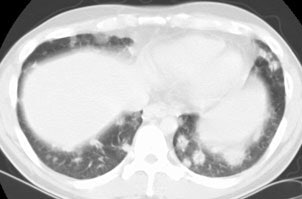

The patient below presented with complaints of cough, malaise, and a low-grade fever. The chest radiograph revealed some patchy left lower lobe airspace disease and vague nodular shadows- particularly in the lower lung zones. A chest CT was performed and demonstrated multiple nodular airspace abnormalities with variable margins. The lesions did not improve despite antibiotic therapy and all cultures were negative. Click images to enlarge. |

Open lung biopsy confirmed the diagnosis of BOOP. Following institution of therapy with steroids the lung lesions resolved. Click images to enlarge.